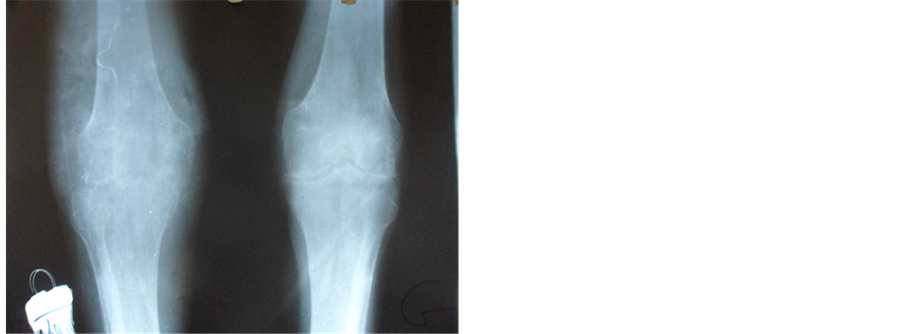

The X-ray of the hands, the front feet and the left knee objectified a stern destructive gouty arthropathy (Figure 2). At the right knee, they showed a stern septic synovitis with complete disappearance of the joint spacing, important diffuse demineralization and erosion of the external tibial tray (Figure 3). The MRI of the right knee confirmed arthritis with articular spring (Figure 4).

Figure 3. X-ray of the two knees giving prominence to a destructive arthritis.